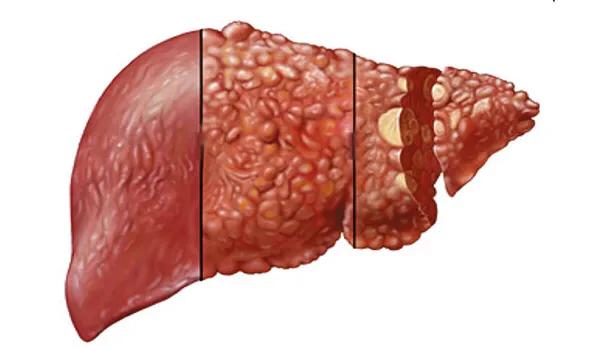

Les personnes obèses sont plus susceptibles d'être accompagnées d'une stéatose hépatique, qui concerne près de 30 % des adultes en Chine. Nous savons que la stéatose hépatique peut devenir cancéreuse si elle n'est pas activement contrôlée : stéatose hépatique → stéatohépatite → fibrose hépatique → cirrhose → cancer du foie. Certaines études montrent que les patients atteints d'un cancer du foie causé par une stéatose hépatique ont une période de survie plus courte et ont moins de chances de recevoir une greffe de foie.

L'alcool "blesse le foie" devrait faire partie des lésions chimiques du foie, dont les principales manifestations sont la stéatose hépatique, le foie alcoolique, l'hépatite, la cirrhose et le cancer du foie.

Deuxièmement, la consommation fréquente d'aliments contenant une grande quantité de graisse animale, un régime excessif contenant des aliments gras, le métabolisme du corps n'est pas consommé, il sera stocké dans le foie et la formation de graisse sous-cutanée, le foie contient trop de graisse se traduira par le foie gras, le foie gras ~ cirrhose ~ cancer du foie, le processus que l'incidence d'un foie sain est plusieurs fois plus élevé.